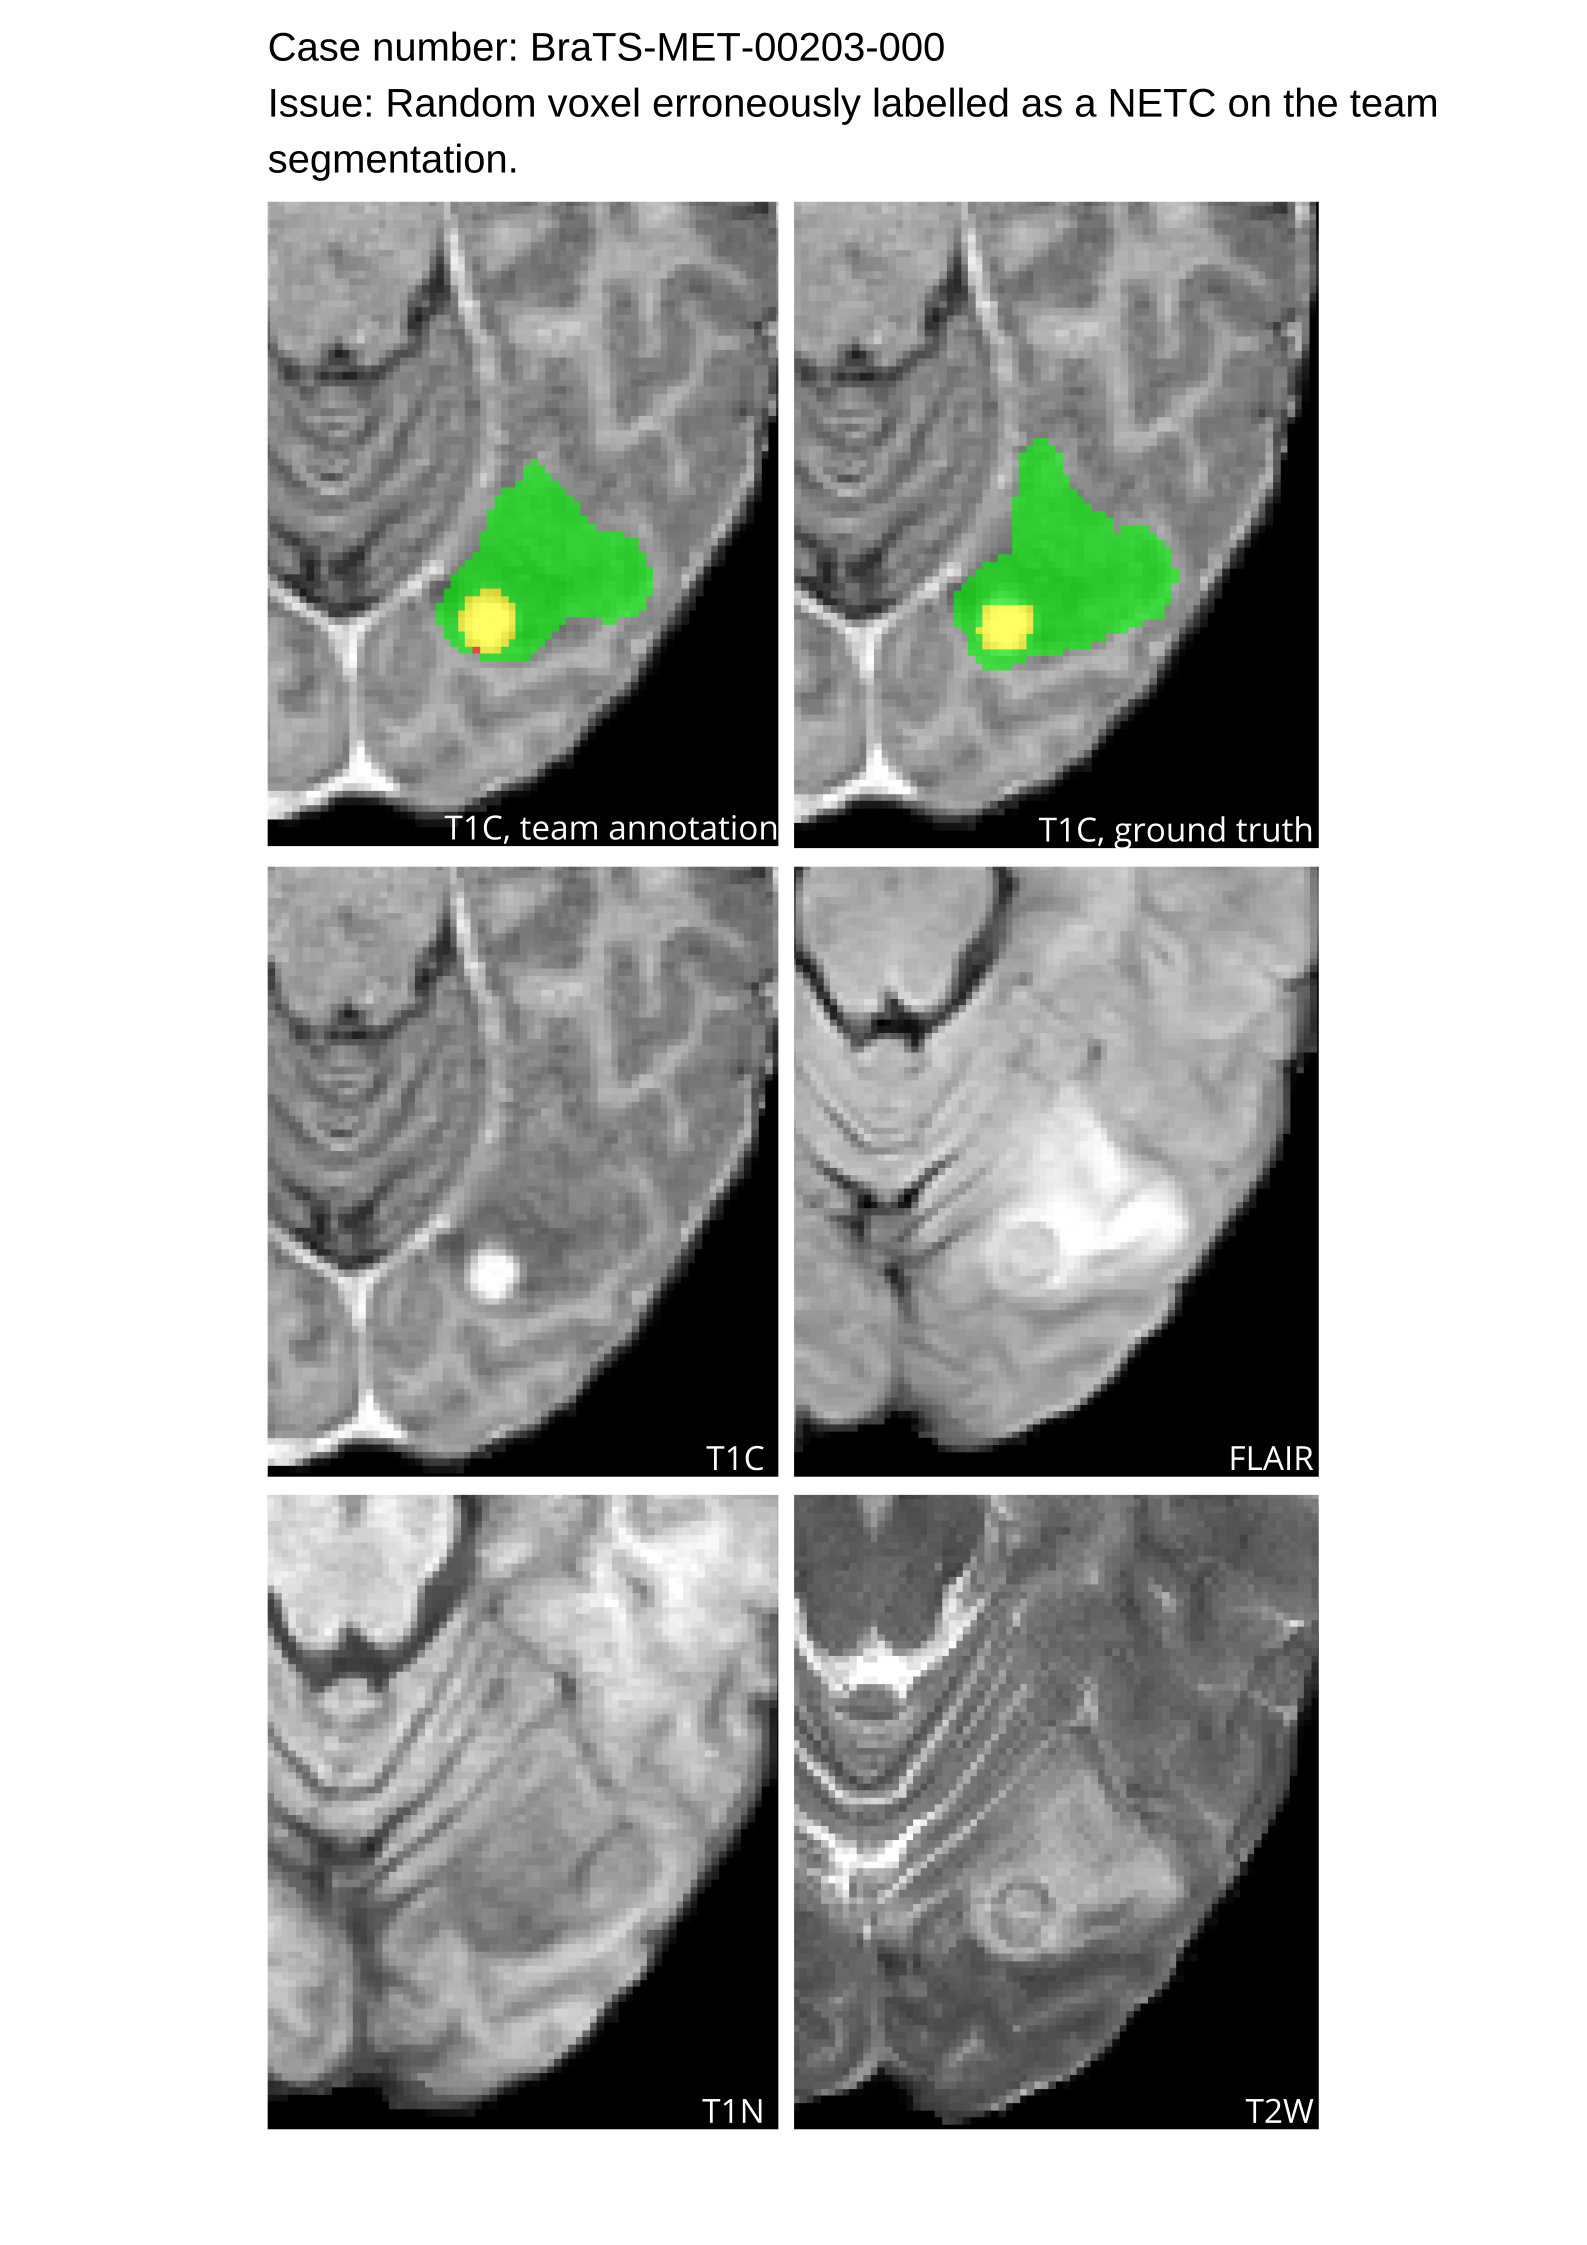

Approvers reviewed the volunteer annotations and either approved the case or returned it to students for re-annotation. Additionally, a QC process was implemented, which included removing all random voxels and any voxels outside the brain mask, ensuring all images had the same parameters (space, orientation, and origin) as the SRI24 atlas, and verifying the presence of all segmentations and segmentation masks are in the folder with original NIfTI images.

Acknowledging the variability in lesion significance arising due to human error, a volumetric threshold of 2 voxels (2 mm3superscriptmm3\text{mm}^{3}mm start_POSTSUPERSCRIPT 3 end_POSTSUPERSCRIPT) was established by an expert panel of clinical radiologists, below which the models’ performance on deemed ”small/false” lesions is not considered in the evaluation. This approach was primarily adopted to ensure that participants were not unfairly penalized for stray voxels in the GT labels, which may result from human error, or for small lesions unrelated to the pathology central to the challenge. The expert panel of clinical radiologists also determined the dilation factor, which was uniformly applied for combining lesions in the GT masks. A dilation factor of 1 voxel in 3D space was chosen because BMs can be small, and it is important to avoid combining these small BMs.